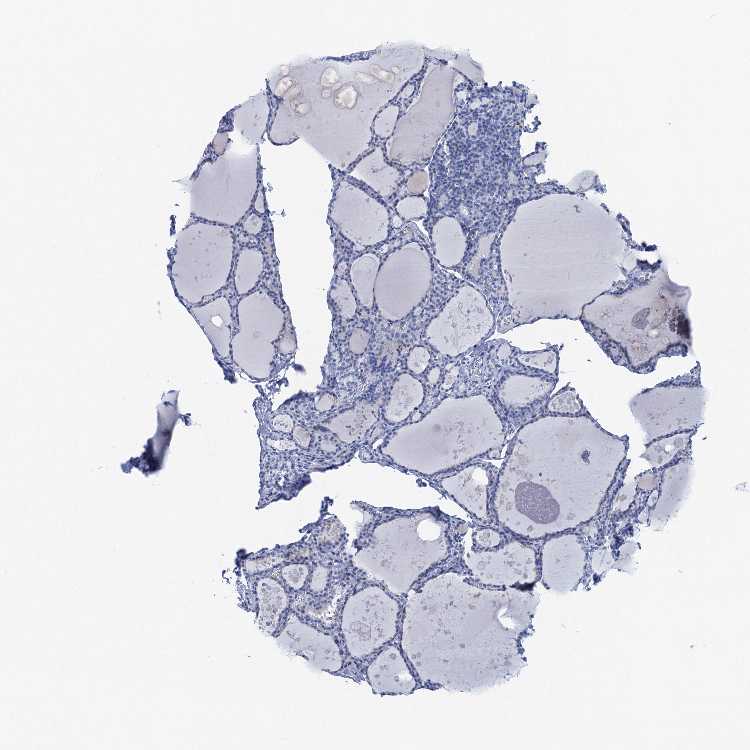

TISSUE PRIMARY DATA THYROID GLAND Show tissue menu

THYROID GLAND - Antibody stainingi

Antibody staining in the annotated cell types in the current human tissue is reported as not detected, low, medium, or high, based on conventional immunohistochemistry profiling in selected tissues. This score is based on the combination of the staining intensity and fraction of stained cells.

Each image is clickable and will lead to virtual microscopy that enables deeper exploration of all samples and also displays staining intensity scores, fraction scores and subcellular localization as well as patient and tissue information for each sample.

Antibody HPA039498Antibody HPA040101

Glandular cells Not detectedHigh